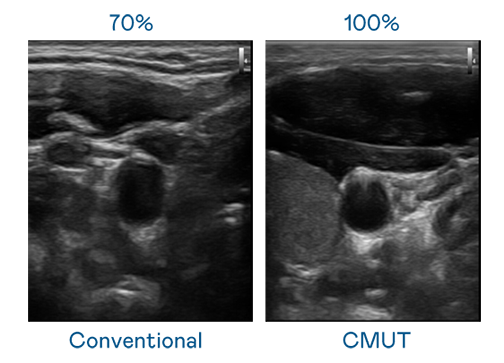

CMUT 技术是一种用电容式微机电元件来产生超音波讯号的技术。与传统 PZT 压电式技术相比,CMUT 频宽增加 30%,更宽频的超音波讯号让影像解析度大幅提升,是实现高影像品质医疗超音波扫描、促进精准医疗发展的关键技术。

大频宽带来超清晰影像

超音波影像的解析度高低,首先取决于探头能发出的讯号频宽。九州酷游 CMUT 可提供高清晰的超音波讯号,提供高频宽、高灵敏度、影像纹理细节更高的超音波影像,协助医护人员缩短影像判读时间及利用精准的医疗影像进行诊断。